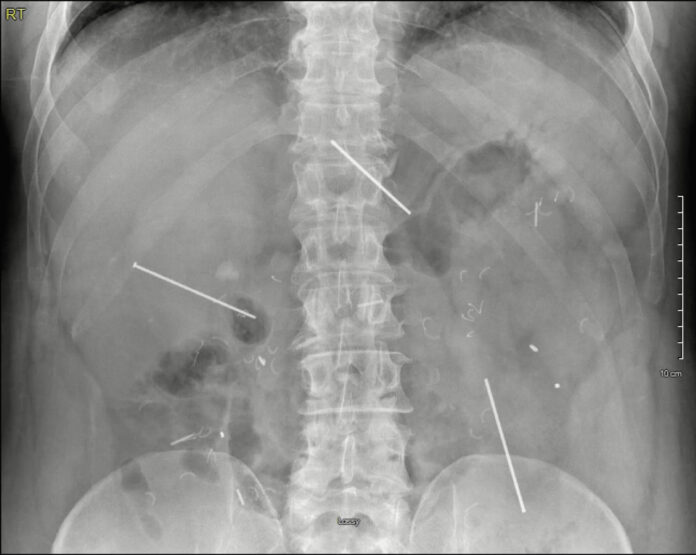

Спустя несколько недель легкий дискомфорт заставил пациента обратиться за помощью. Первичный осмотр не выявил критических нарушений, но повторное обследование с применением рентгена и КТ показало шокирующую картину: три гвоздя располагались в области печени, поджелудочной железы и кишечника. Удивительно, но анализы оставались в норме, а признаки воспаления отсутствовали.

Во время операции врачи аккуратно извлекли инородные тела, избежав повреждения внутренних органов. Один гвоздь пронзил печень и поджелудочную, другой остановился возле двенадцатиперстной кишки, третий застрял между петлями кишечника. Процедура прошла без осложнений, а восстановление пациента заняло минимальное время.